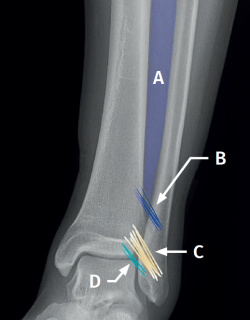

Figure 1. Schematic representation of the anterior syndesmosis. A: interosseous membrane; B: interosseous ligament; C: anterior tibiofibular ligament; D: distal fascicle of the anterior tibiofibular ligament.